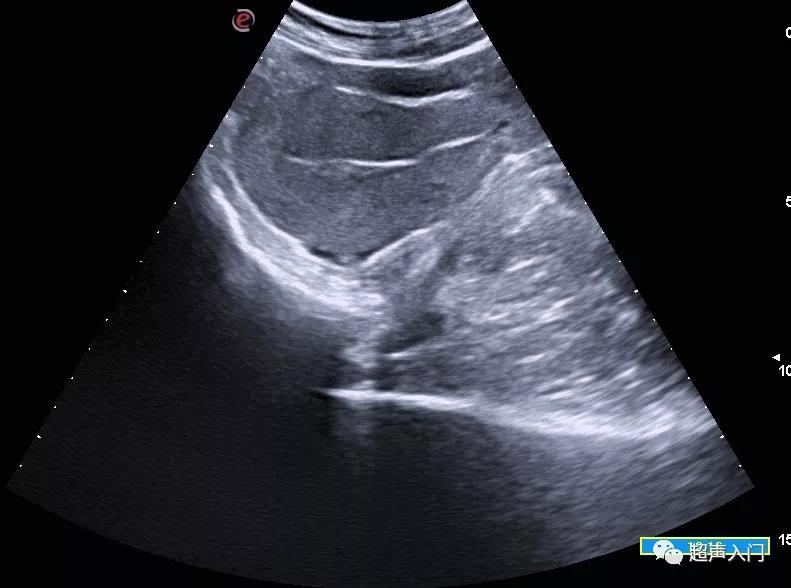

平位子宫: 纵切面子宫呈水平位,宫体宫颈之间的角度几乎消失。

平位子宫(经腹纵切面)

早孕,平位子宫(经腹纵切面)